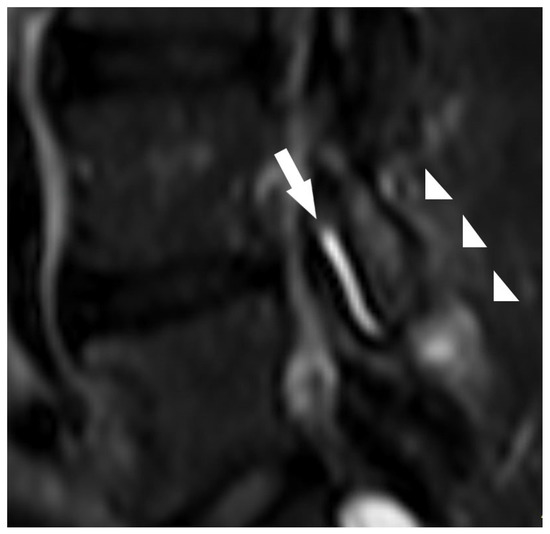

- Type of ligamenta flava with axial loading;

| Ligamentum flavum type (typical, atypical) | Typical (thickness < 5 mm and area < 55 mm2) | 24 | 26.7 |

| Typical (thickness ≥ 5 mm and area ≥ 55 mm2) | 26 | 28.9 | |

| Atypical (thickness < 5 mm and area ≥ 55 mm2) | 38 | 42.2 | |

| Atypical (thickness ≥ 5 mm and area < 55 mm2) | 2 | 0.2 | |

| Atypical ligamenta flava (thickness < 5 mm; area ≥ 55 mm2) | 1.753 | 0.593 | 0.003 | 5.771 | 1.804 | 18.461 |